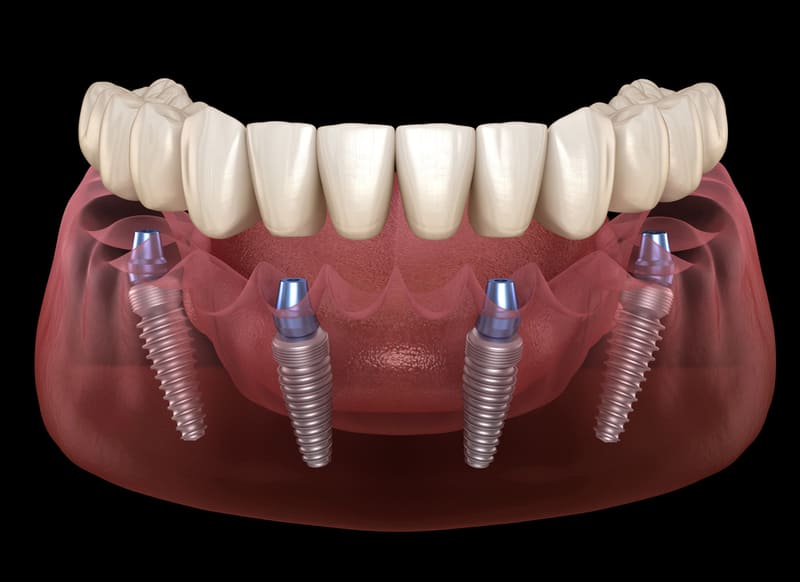

The All on 4 dental implant procedure typically takes several appointments over the course of several months. The exact duration will depend on the individual case and the number of implants needed.

The procedure is generally not painful, as dental implant surgery is typically performed under local anesthesia or IV sedation. However, some discomfort and swelling can be expected after the procedure.

After the procedure, the patient will be given specific instructions for caring for the surgical sites, including information about diet and oral hygiene. The patient will also be given a follow-up schedule to ensure that the healing process is progressing as expected.